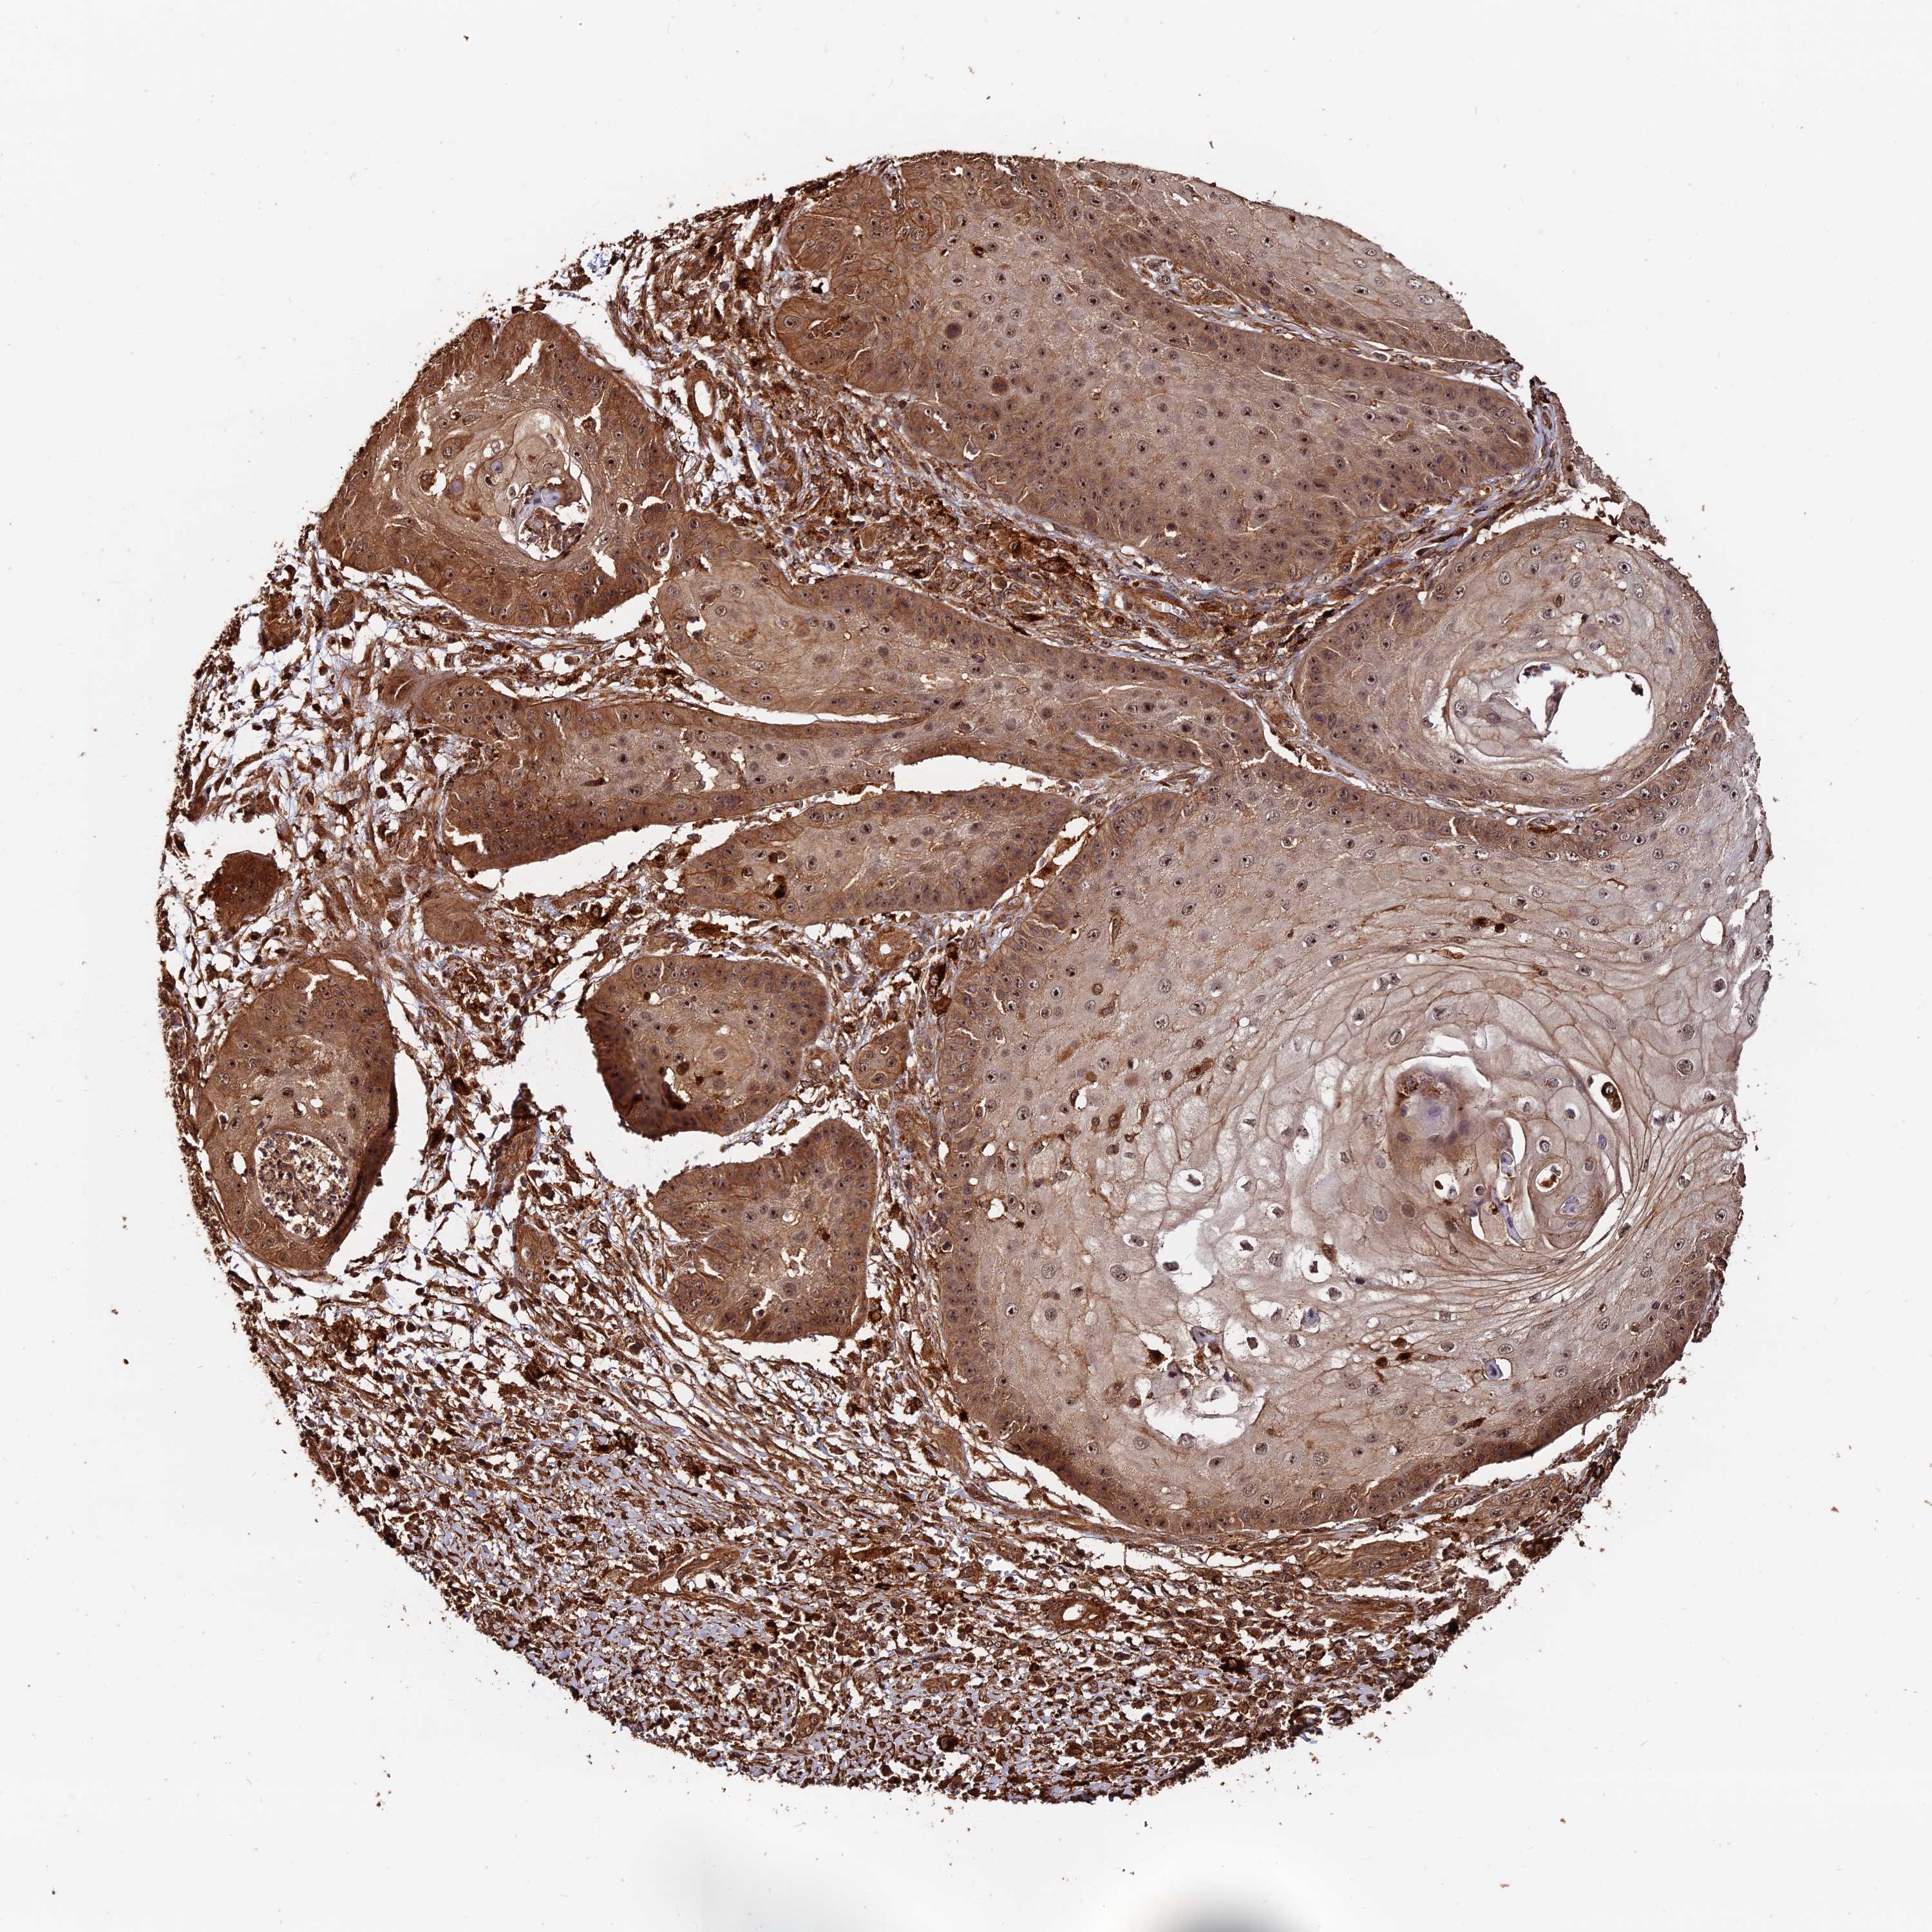

Basal cell and squamous cell cancer

SKIN CANCER - Protein expressioni

A mouse-over function shows sample information and annotation data. Click on an image to view it in a full screen mode. Samples can be filtered based on level of antibody staining by selecting one or several of the following categories: high, medium, low and not detected. The assay and annotation is described here.

Antibody stainingi

Antibody staining in the annotated cell types in the current human tissue is reported as not detected, low, medium, or high, based on conventional immunohistochemistry profiling in selected tissues. This score is based on the combination of the staining intensity and fraction of stained cells.

Each image is clickable and will lead to virtual microscopy that enables deeper exploration of all samples and also displays staining intensity scores, fraction scores and subcellular localization as well as patient and tissue information for each sample.

Antibody CAB002611

Squamous cell carcinoma, NOS